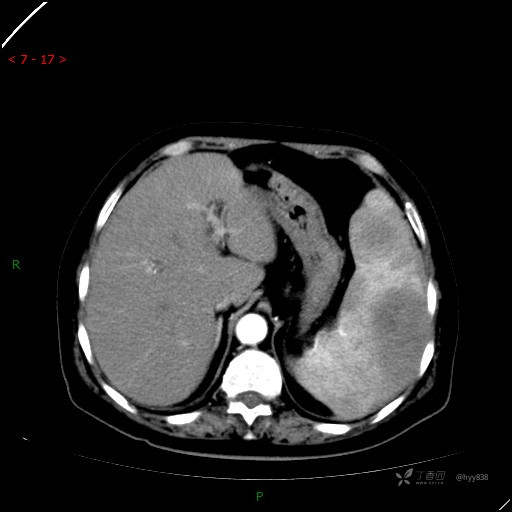

静脉期